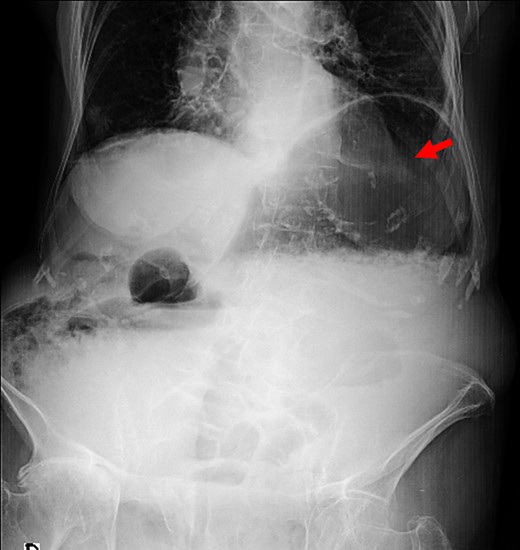

The patient underwent an abdominal plain film, which identified a massive gastric dilation and a pneumoperitoneum was suspected (Fig. 1). In order to confirm these findings, an abdominal computed tomography (CT) was performed, which clearly identified a massive gastric dilation. The stomach reached the pelvis and had an abrupt stricture at the level of the pylorus. A large pneumoperitoneum was also confirmed (Fig. 2).

Plain abdominal film with massive gastric distension (red arrow).